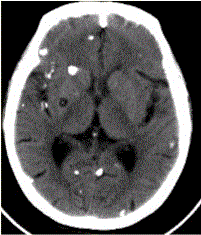

问题 患者男,45岁。头痛、癫痫10余年。查体:无发热,双侧肢体肌力正常。脑电图示双侧额颞叶棘波放电。CT表现如下图。 脑囊虫病按部位分可分为

选项 A.脑实质型 B.蛛网膜下腔型 C.脑室型 D.脑膜型 E.混合型 F.囊泡型 G.钙化型

答案 ACDE